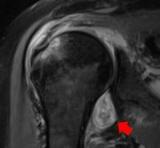

核磁共振成像显示,年轻痴呆症患者的大脑奖赏回路退化

磁共振图像显示,快感缺失是额颞叶痴呆的一个显著临床特征,与冷漠或抑郁患者不同脑区(眶额叶皮层,前扣带皮层,脑岛和纹状体)的灰质强度降低相关。 2021-05-25 辐射成像